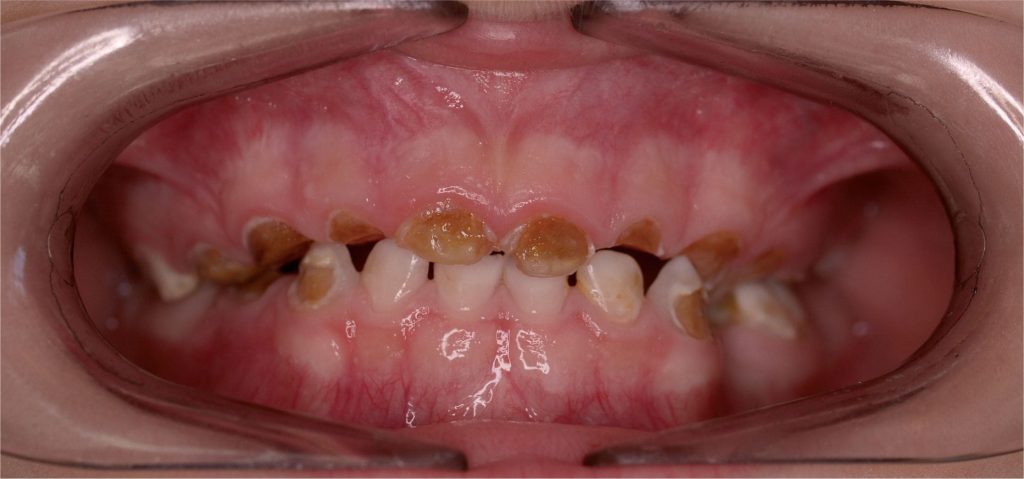

- Como se desarrolla en el espacio entre dos dientes, este tipo de caries normalmente afecta los dos dientes como se muestra a continuación: